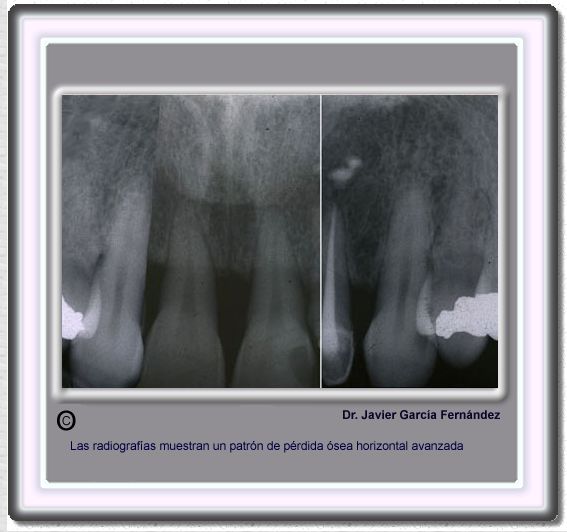

image102